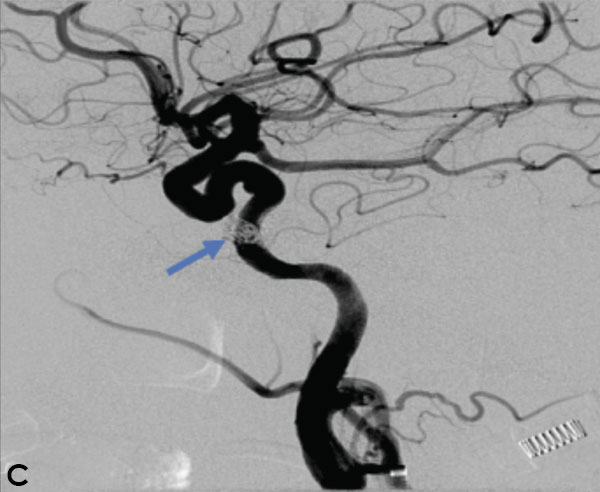

Collateral venous drainage into the orbit and skull base was observed (Figure A). After successful cannulation of the direct aperture between the right carotid artery and the cavernous sinus, balloon-assisted coil embolization of the posterolateral compartment was performed until the fistula was closed (Figure B and C). He experienced immediate cessation of his pulsatile tinnitus with an early improvement of the right VI nerve palsy and near-complete recovery of his vision within 6 weeks

Figure: (A) Right ICA Cavernous Fistula with Venous Shunting (B) Balloon Assisted Coil Embolization (C) Fistula Cured Post Embolization

A 59-year-old man who is otherwise healthy presented to his PCP with progressive right-sided pulsatile tinnitus for 4-6 weeks. His PCP and ENT evaluated him extensively and prescribed multiple courses of steroids and subsequent unremarkable MRI and MRA imaging. He developed acute onset diplopia secondary to a new partial right VI nerve palsy several days prior to our evaluation. A cerebral angiogram confirmed the presence of a high flow direct fistula of the right internal carotid artery–right cavernous sinus.